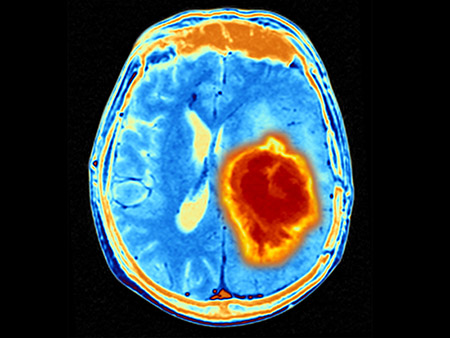

Brain tumors are the most common solid tumor in children, and aggressive types like glioblastoma have an extremely low survival rate: as low as 10 percent five years after diagnosis. Even tumors successfully treated by surgery, radiation and/or chemotherapy have a high recurrence rate.

In the Phase 1 clinical trial of 12 patients between 7 and 18 years of age, the investigators employed a modified virus known as G207, derived from the herpes virus responsible for cold sores. The virus is genetically altered so that it infects only tumor cells. When injected into a malignant brain tumor via a catheter, the virus enters the tumor cells and replicates. This kills the cell and releases the virus’s progeny to hunt out other tumor cells. Additionally, the virus induces a strong immune response by the body’s immune system, which can attack the tumor. The trial tested G207 alone and then combined with a single low-dose of radiation designed to increase virus replication and spread throughout the tumor.

In the current trial, 11 of the 12 patients demonstrated a treatment response. The overall survival rate was more than double the typical survival rate for children with high-grade glioma. Some 36 percent of the patients thus far have survived longer than 18 months, surpassing the medial overall survival for newly diagnosed patients with high-grade glioma.